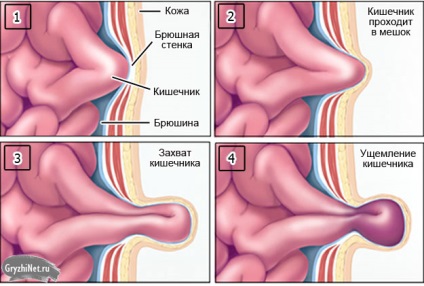

Educație și hernie strangulata

Motive pentru încălcarea și speciile sale

Pe mecanismul de hernie strangulată in zona abdomenului, la fel ca oricare alta, este de 4 tipuri.

1. încălcarea elastică

ciupirea elastică are loc atunci când o creștere bruscă a presiunii abdominale. Motivele pentru acest lucru este simplu: tuse, strănut, entorse bruște ale corpului, ridicarea de greutati, efortul de defecatie, etc ...

Cu varietate de încălcări în sacul herniar afară mai mult conținut decât de obicei, și nu poate veni înapoi. organe la stânga a fost transferat de inel herniar are loc în acesta anoxia (ischemie), care, în lipsa asistenței adecvate devine țesuturi de necroză (necroză).

atribut indispensabil al încălcării elastice - herniar foarte îngust.